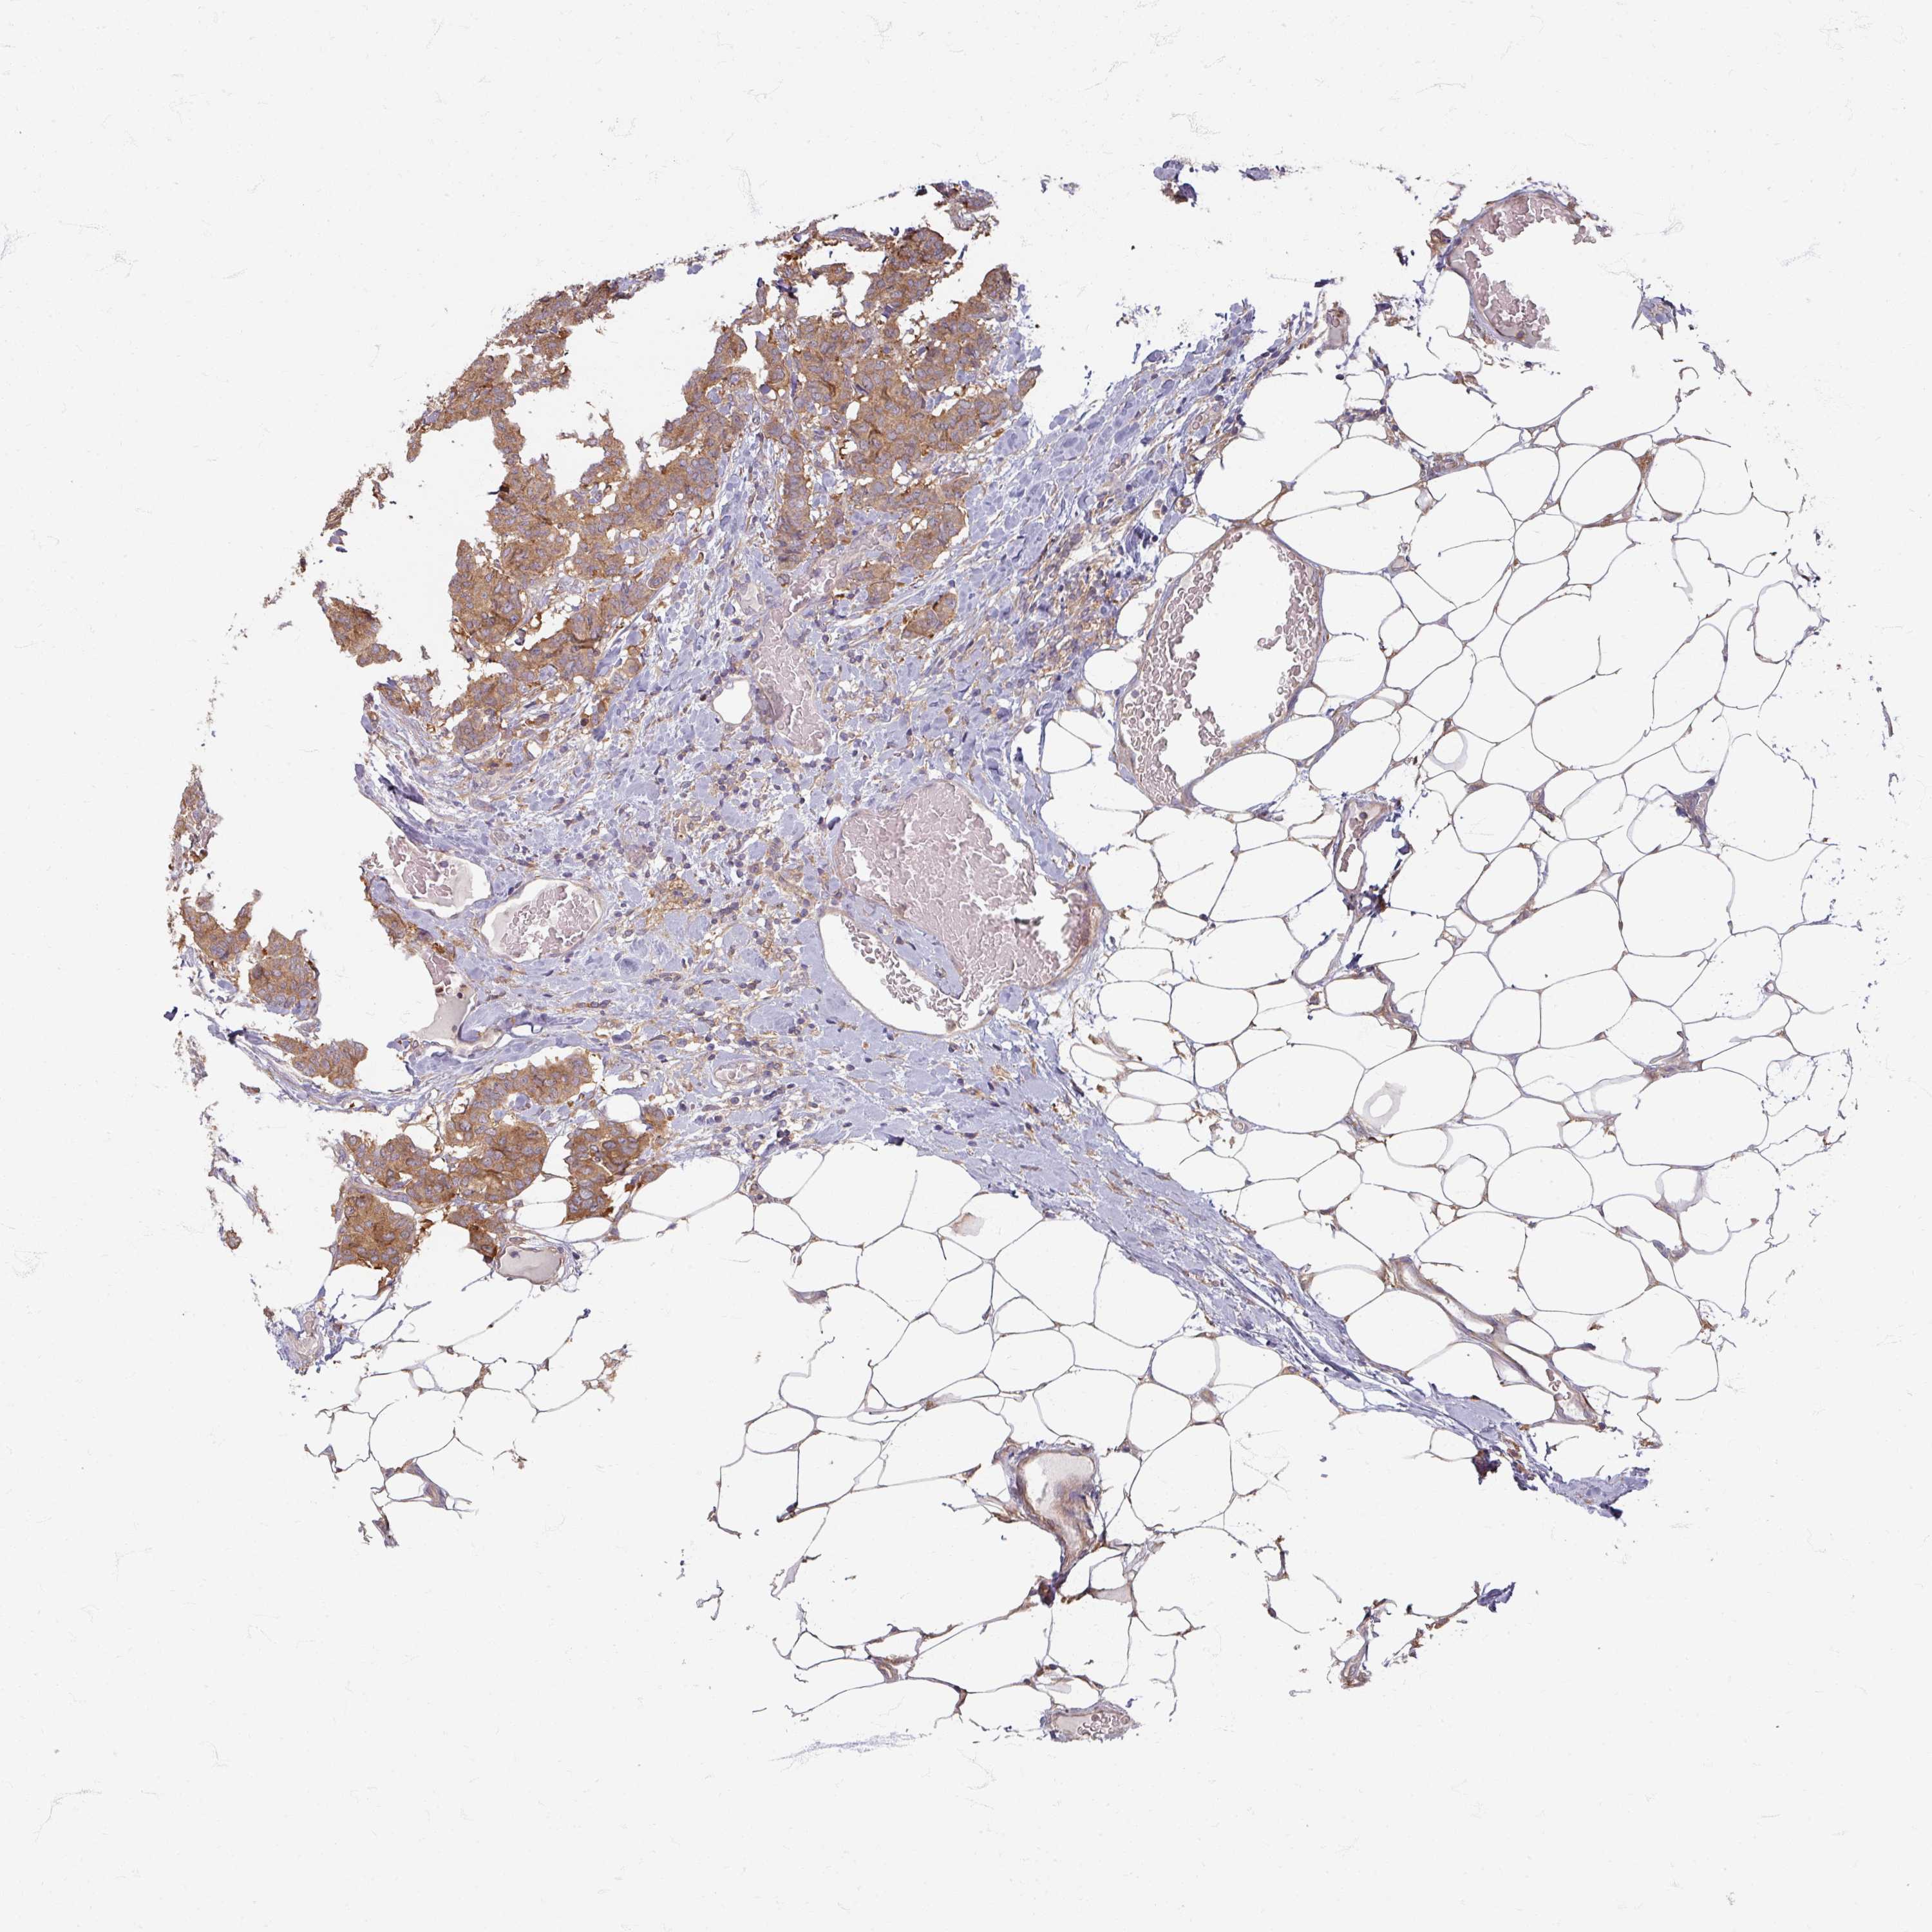

CANCER BREAST CANCER Show tissue menu

BRCA TCGA BRCA VALIDATION PROTEIN EXPRESSION